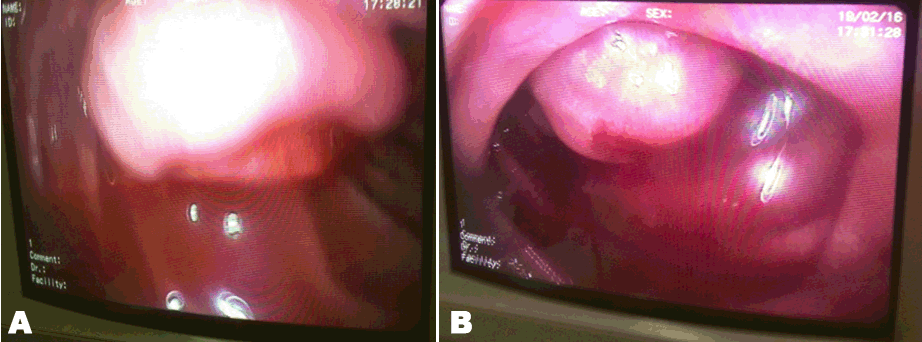

Malignant melanoma are tumors that derived from melanocytes. Malignancy will grow irregularly and then might function made abnormally. Melanoma will produce pigment in varying number and can elicit immune response of the body. When the immune response decreased might function made clinical appearance would worsen (Figure 1, Figure 2).

Figure 1: (A and B): Clinical picture of melanoma maligna of the left calcaneal region in patient male, 72-years-Old.